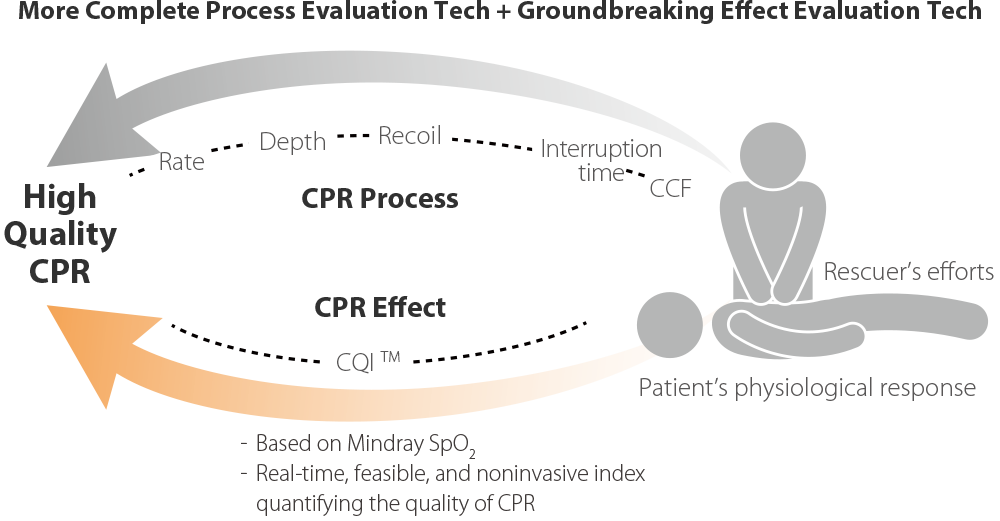

Rettungsdreieck, Umfassender

Schnellere Wiederbelebung